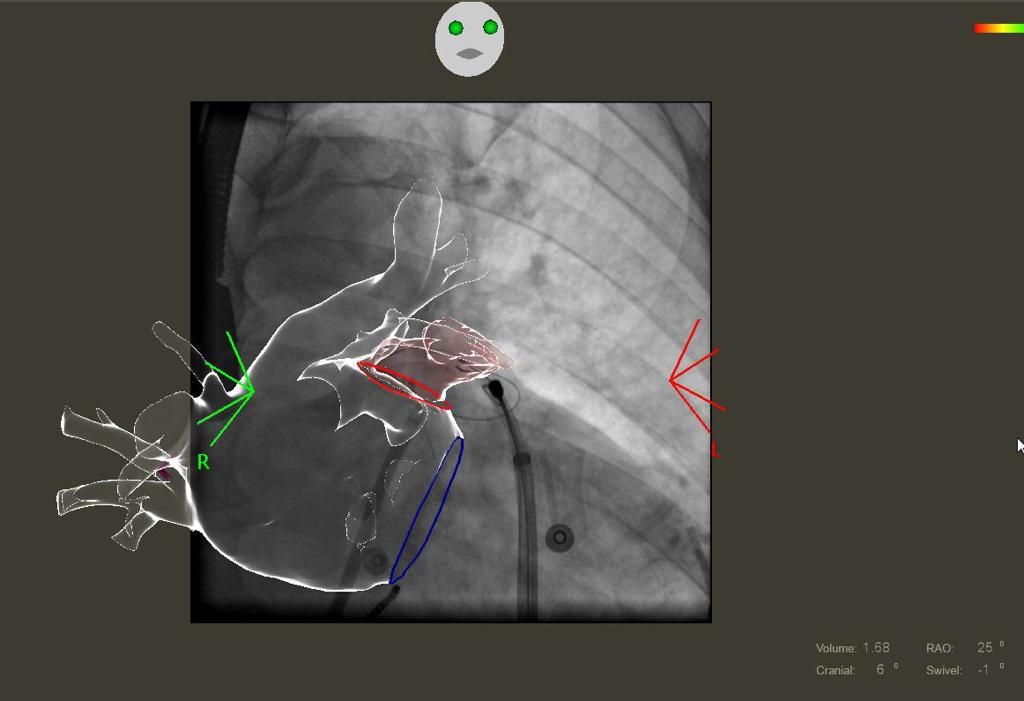

Lotta alla fibrillazione atriale: al Mauriziano un intervento unico al mondo salva la vita a un 56enne

L'operazione, eseguita dal dottor Stefano Grossi, rappresenta una novità assoluta per il trattamento della patologia e che punta ad abbattere il rischio ictus

Per la prima volta al mondo, al Mauriziano intervento rivoluzionario salva la vita ad un paziente 56enne